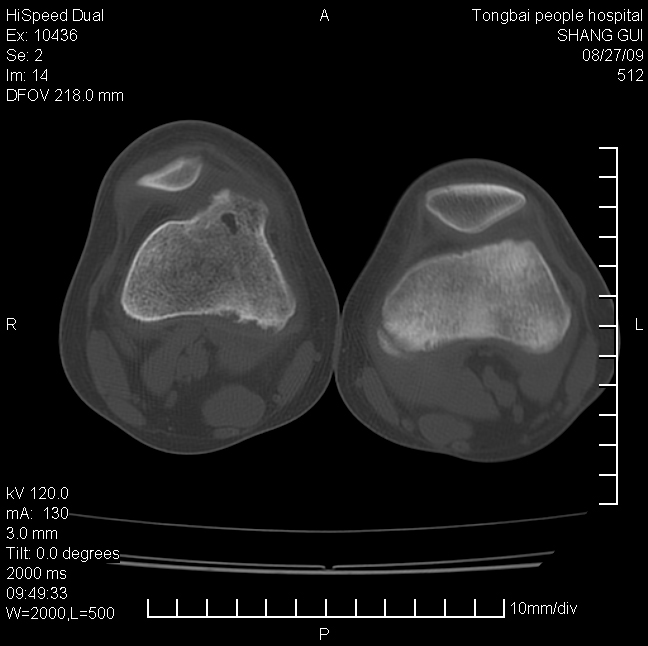

女,12岁。无意发现股骨下端隆起。局部皮肤颜色,温度无异常。

考虑右股骨下端骨纤维结构不良;不排除非骨化性纤维瘤。

不能排除,其实平片更直观。宽基底骨软骨瘤皮质与骨干皮质相连,髓腔与髓腔相通,骨纹理走行方向一致,部分软骨帽可有钙化,本例病变内“磨玻璃状、多囊状改变”比较符合骨纤。